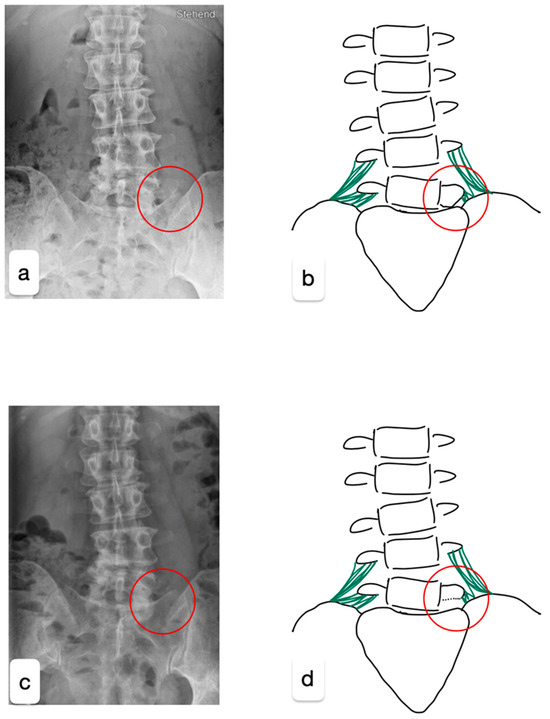

Figure 1. X-rays in the anteroposterior projection before (a) and after the surgery (c), supplemented by a graphical simplification of the imaging (b,d). The red circle highlights the location of the LSTV. The surgery aimed to release the existing connections between the pelvis and the malformed transverse process of L5 while preserving the iliolumbar ligament (green) through microsurgical techniques to maintain stability.

A 48-year-old healthy female triathlete presented to our outpatient clinic with pain in the left gluteal region persisting for two years, especially during sporting activities. No relevant past medical history. Neurological examination of the patient was unremarkable, showing normal flexibility and mild tenderness over the left sacroiliac joint. Magnetic resonance imaging and computed tomography revealed multisegmental degenerative changes with a right convex scoliosis, multisegmental disc extrusion without relevant stenosis, osteochondrosis L2/3, L4/5, and L5/S1, facet joint arthrosis L3/4, and left-sided LSTV (Castellvi type 1a) (Figure 1a,b).

As the conservative treatment was exhausted, surgical reduction of the left L5 transverse process was performed. For the surgery with general anesthesia, the patient was positioned in a prone position on a Wilson frame. The L5/S1 neoarticulation was visualized using X-ray control (anterior–posterior and lateral beam path). Following a paramedian skin incision on the left L5/S1 level and dissection of the fascia and paravertebral musculature, a Caspar retractor was inserted. The caudal part of the transverse process L5 was reduced microsurgically using a 6 mm diamond drill and bone punch (Figure 1 and Figure 2). Strong adhesions to the pelvis were exposed and the L4 nerve root could be visualized.